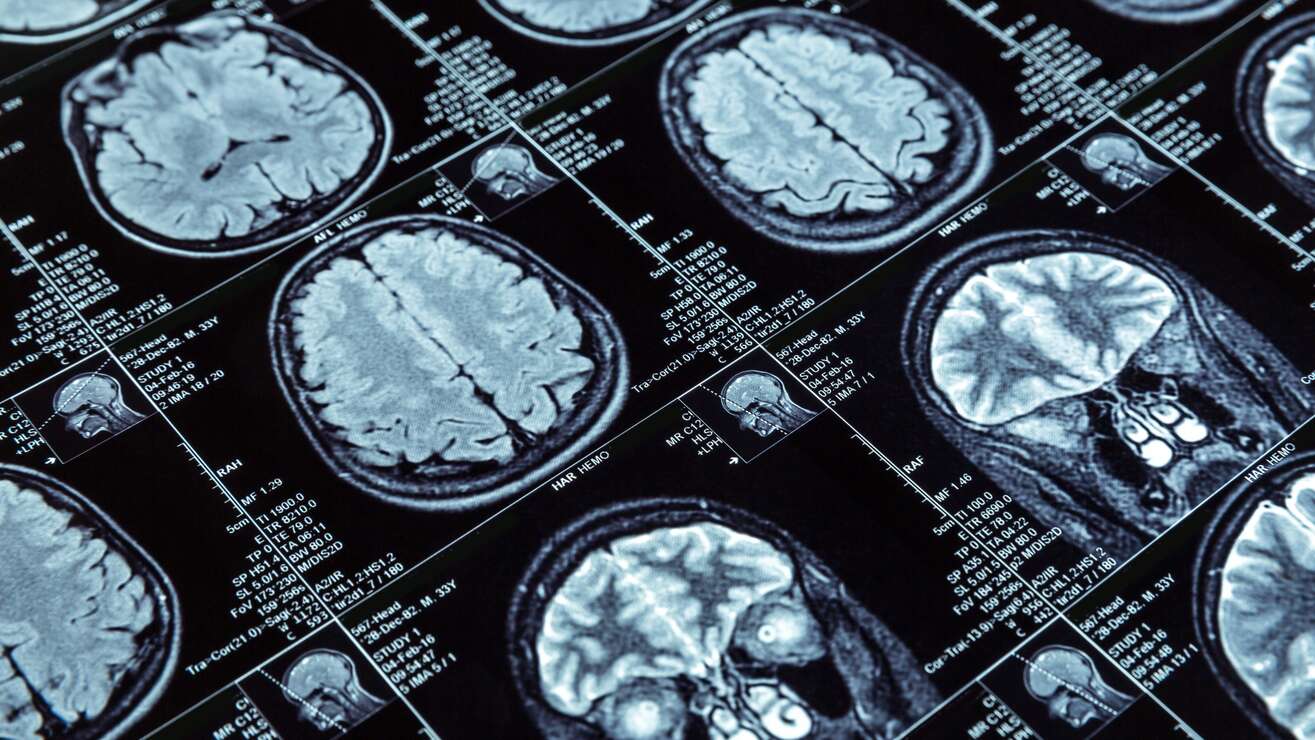

New research seems to offer some long-sought insights into the perplexing and devastating condition known as myalgic encephalomyelitis, also called chronic fatigue syndrome. The National Institutes of Health-led study found several potentially key differences in the brains and immune systems of people with ME/CFS compared to healthy controls. The findings could help point to possible future treatments, the researchers say.